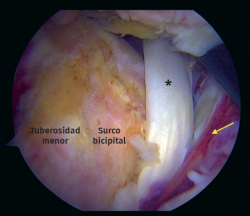

Figura 2. Vista artroscópica desde el portal anterolateral en un hombro derecho en posición de silla de playa. Rotura crónica del tendón del bíceps. Flecha: espesor total y retracción del tendón subescapular.

Figura 5. Vista artroscópica. Rotura completa del subescapular con inestabilidad medial de la cabeza larga del tendón del bíceps. Asterisco: tendón del bíceps. Flecha: rotura del tendón subescapular.